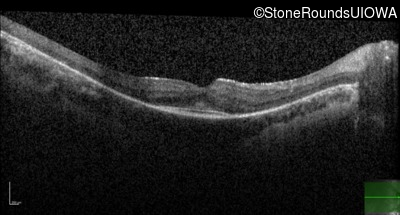

AR Retinitis Pigmentosa (IA1aiii)

Age at visit: 22 years

This 22 year old man noticed some difficulty driving at night during the past year.

Diagnosis & molecular findings

Disease Gene Allele 1 variant(s) Allele 2 variant(s) Inheritance mode

AR Retinitis Pigmentosa CLN3 Deletion Exons 9-10 Arg405Trp CGG>TGG AR